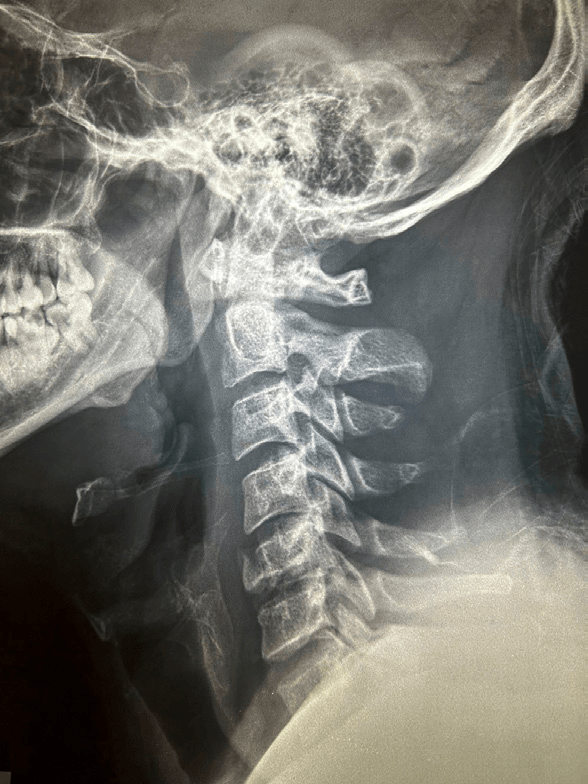

RX lateral de columna cervical (Fig. 1), solución de continuidad en cuerpo vertebral de C5, pérdida parcial de la altura del cuerpo, sin presencia de incongruencia de articulaciones facetarias, pérdida de lordosis cervical. RM simple de columna cervical (Fig. 2), protrusión de disco vertebral C5-C6 y cuerpo vertebral C5 hacia conducto medular.